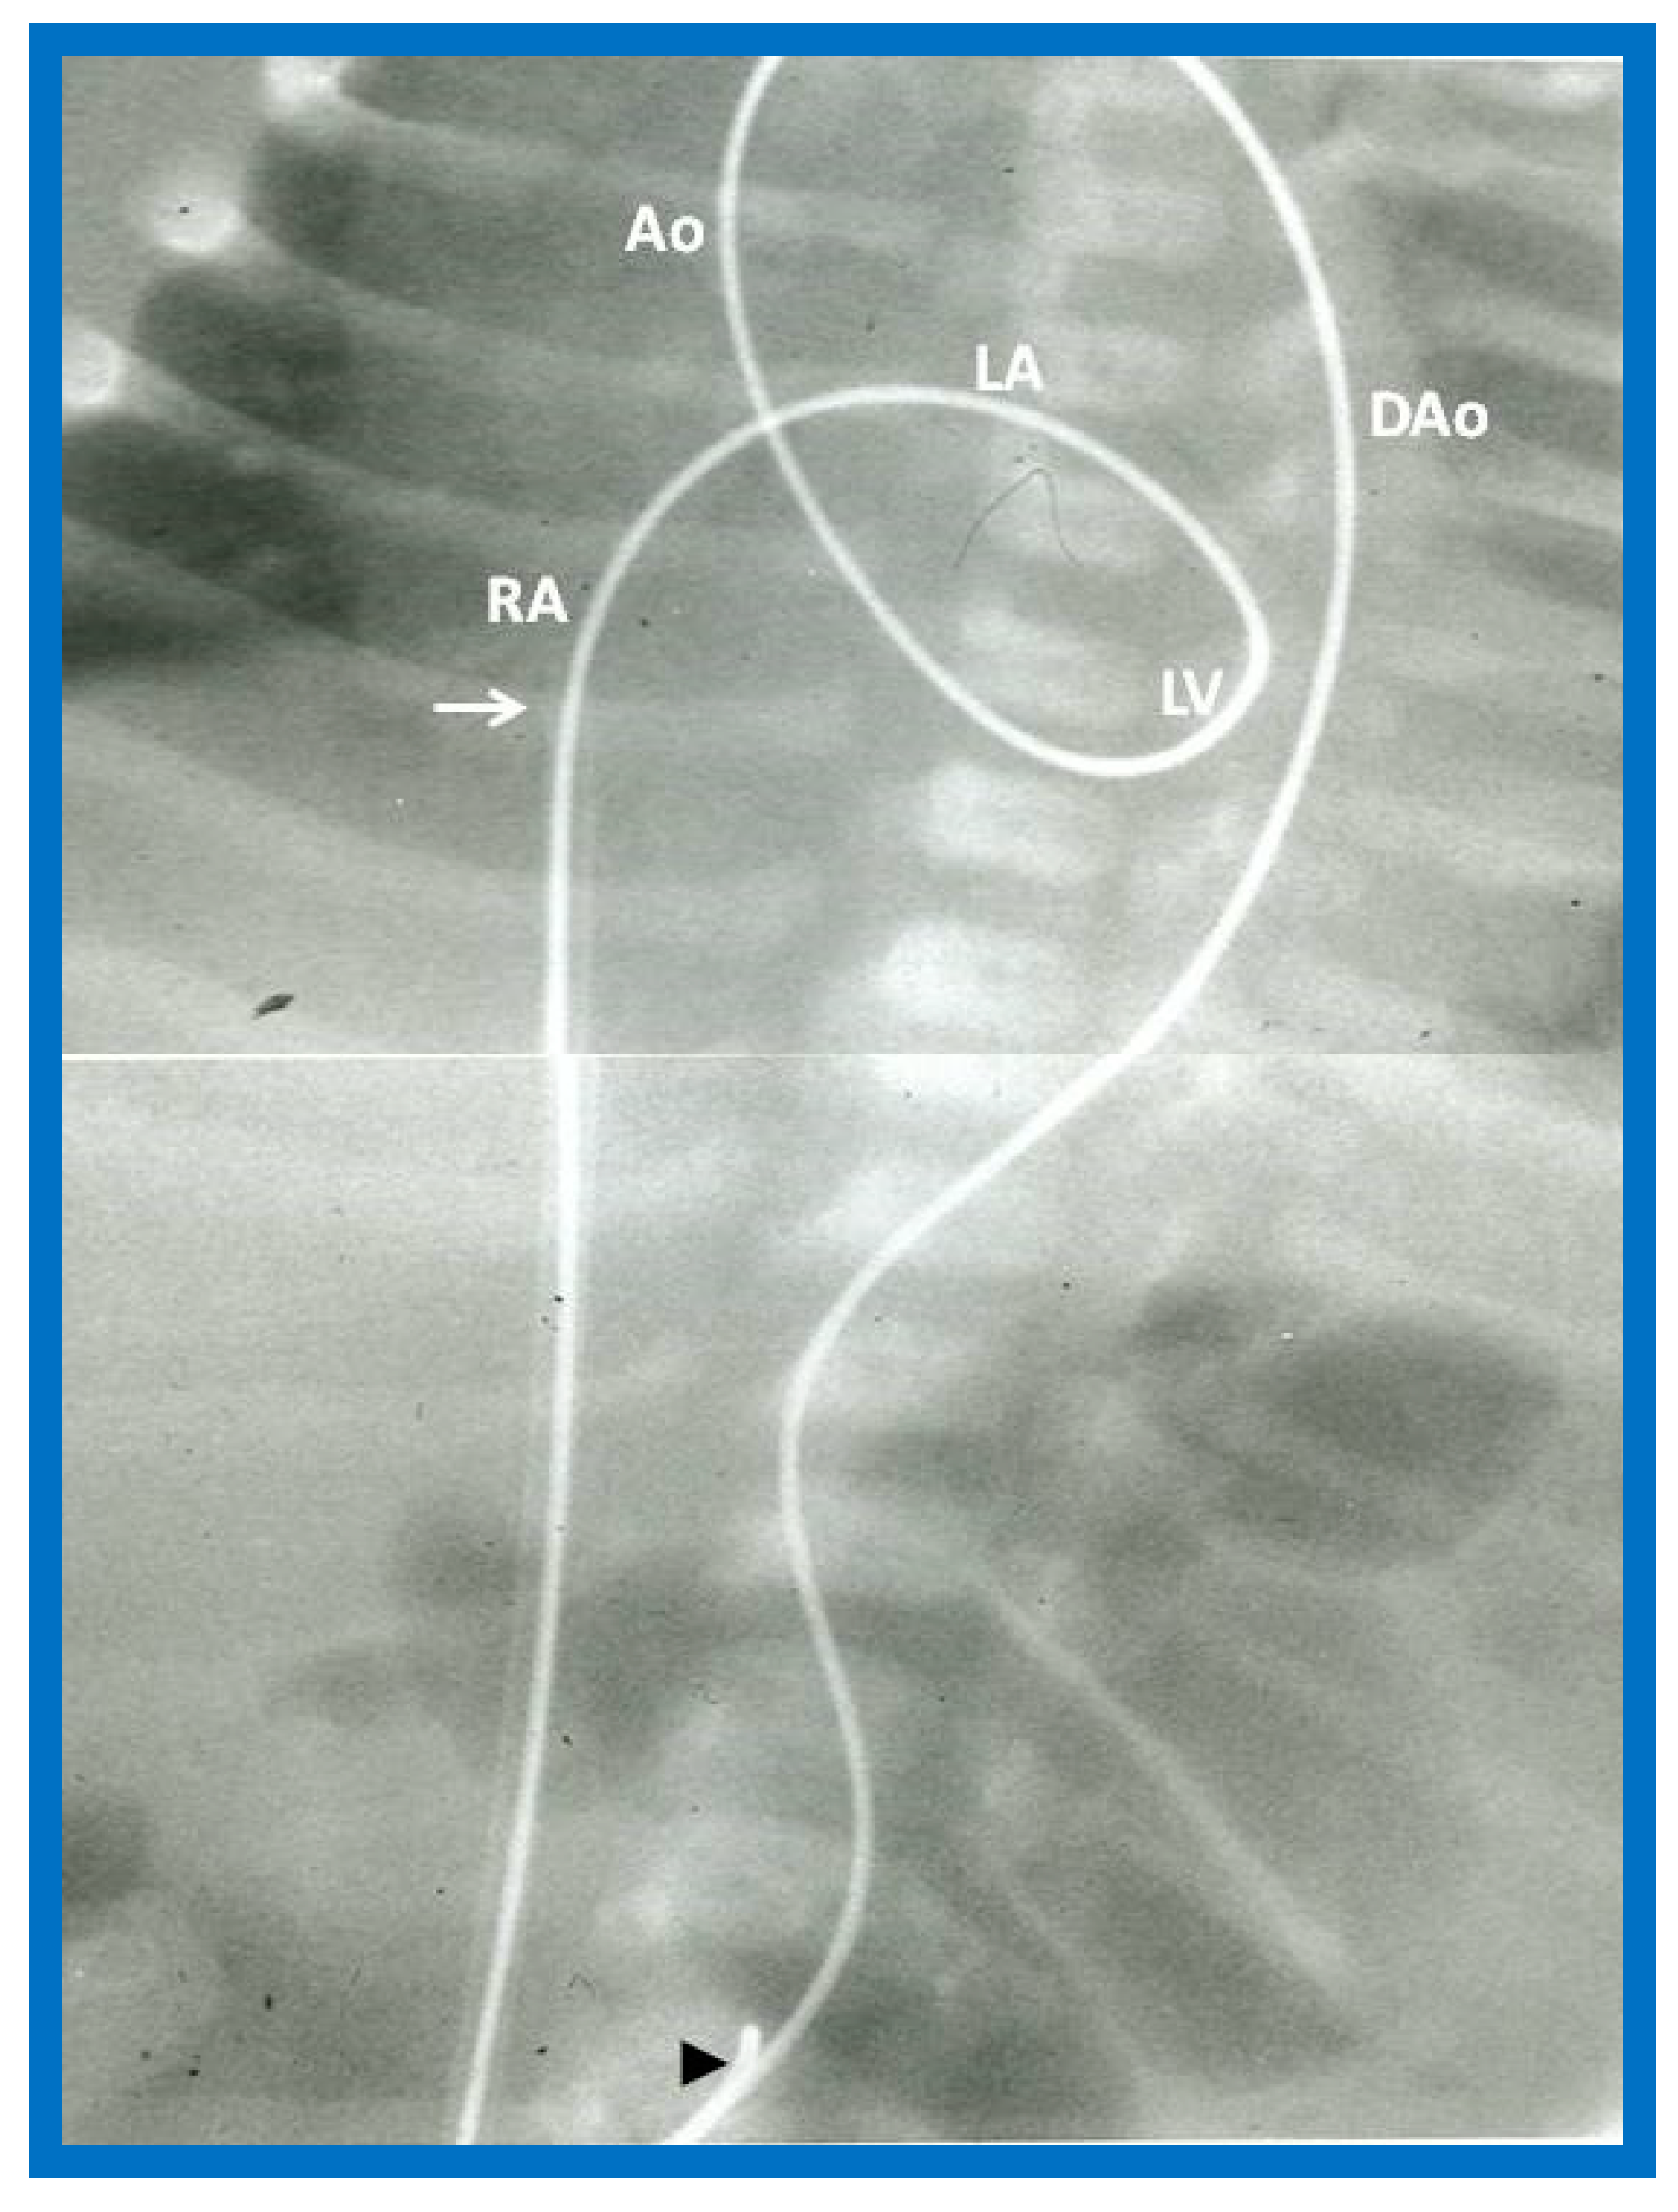

In babies in whom the guidewire cannot be positioned in the descending aorta or the BAV catheter cannot be placed across the aortic valve, a gooseneck micro-snare (Microvena, White Bear Lake, MN) may be sited in the descending aorta either via the femoral or umbilical artery. Then the tip of the anterogradely placed guide wire is snared and pulled down into the descending aorta and held in place. Thus, an umbilical venous-to-umbilical/femoral arterial wire “rail” is created (Figure 29). A mild traction on the descending aortic section of the wire rail facilitates placement of the BAV catheter across the aortic valve. It should be remembered that a wide wire loop in the LV should be maintained during this process. After the BAV procedure is finished, the guidewire is let go from the snare and removed. To prevent injury of the intracardiac structures, a catheter is maintained over the entire course of the guidewire during guidewire withdrawal [55].

The concept of anterograde transvenous approach described by Hausdorf [53] and O’Laughlin [54] and their colleagues was adopted by us; we used the UV instead of femoral vein [55]. We initially thought that creating a guide wire rail (Figure 29) was necessary [55]; however, subsequent experience with the procedure [56,58] demonstrated that such guidewire rail is not necessary, especially in view of availability of less stiff guidewires and more trackable balloon catheters (Figure 30).

Figure 29. The course of the guide wire ‘‘rail’’ from the umbilical vein-to-umbilical artery for positioning the catheter across the aortic valve is demonstrated. The filled arrowhead shows the tip of the snare holding the wire. The tip of the umbilical venous sheath (arrow) is also shown. The wire ‘‘rail’’ courses through the right atrium (RA), left atrium (LA), left ventricle (LV), ascending aorta (Ao) and descending aorta (DAo). Reproduced from Reference [55].